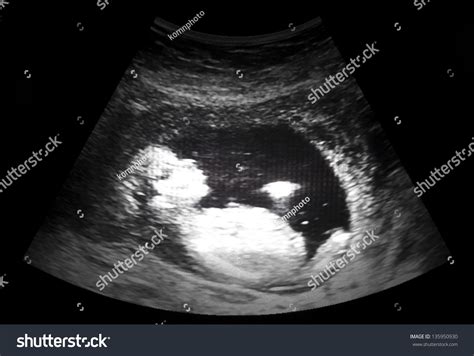

A Thirteen Week Ultrasound is a routine prenatal examination typically performed between 12 and 13 weeks of pregnancy. This ultrasound is crucial for several reasons, including assessing the baby's growth, checking for any potential abnormalities, and determining the due date more accurately. It is often combined with a nuchal translucency scan, which measures the fluid at the back of the baby's neck to screen for chromosomal abnormalities.

During the Thirteen Week Ultrasound, you will lie on an examination table with your abdomen exposed. A gel will be applied to your belly, and a transducer will be moved across the area to capture images of the baby. The procedure is painless and typically takes about 20-30 minutes.

The ultrasound technician will look for several key indicators, including:

• Baby's Heartbeat: The heartbeat should be clearly visible and audible.

• Baby's Measurements: The baby's crown-to-rump length (CRL) will be measured to assess growth and development.

• Placenta Location: The position of the placenta will be checked to ensure it is not covering the cervix (placenta previa).

• Amniotic Fluid Levels: The amount of amniotic fluid will be evaluated to ensure it is within normal ranges.